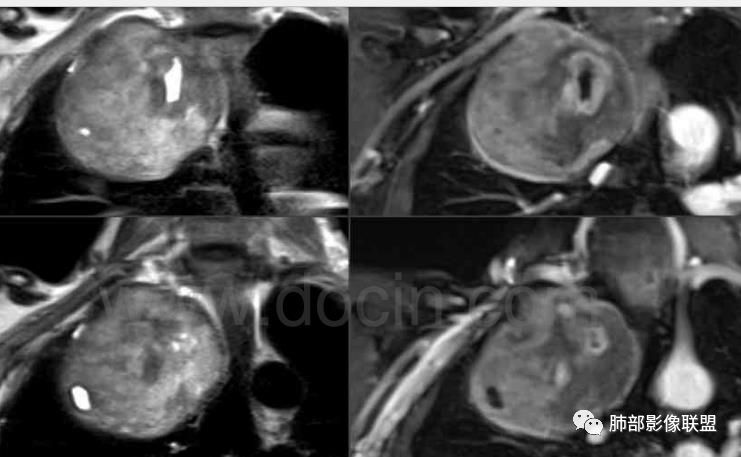

术后病理后纵隔神经鞘瘤

1.左上胸内脊柱旁半圆形肿块,质地坚实,密度比较均匀。

2.病灶周边见胸膜掀起,应当考虑胸壁或是纵隔来源,肺内病变不会如此。

3.降主动脉这一相对固定结构向前方推移,提示病灶相对坚实且有牢固附着点,不支持来自柔软的肺组织。

5.相邻椎间孔未见扩大,也未见块影延入椎管,易起自于神经根的鞘瘤似乎找不到相关支持点。

7.静脉期轻度强化,注意不是环形强化,亦未显示明确的“AB区”,神经鞘瘤与副节瘤亦未找到支持点。

综上,病灶定位胸壁或后纵隔,就发病率而言,神经源性可能性较大。

尚应临床侦查患者有无脑内及皮肤病变。